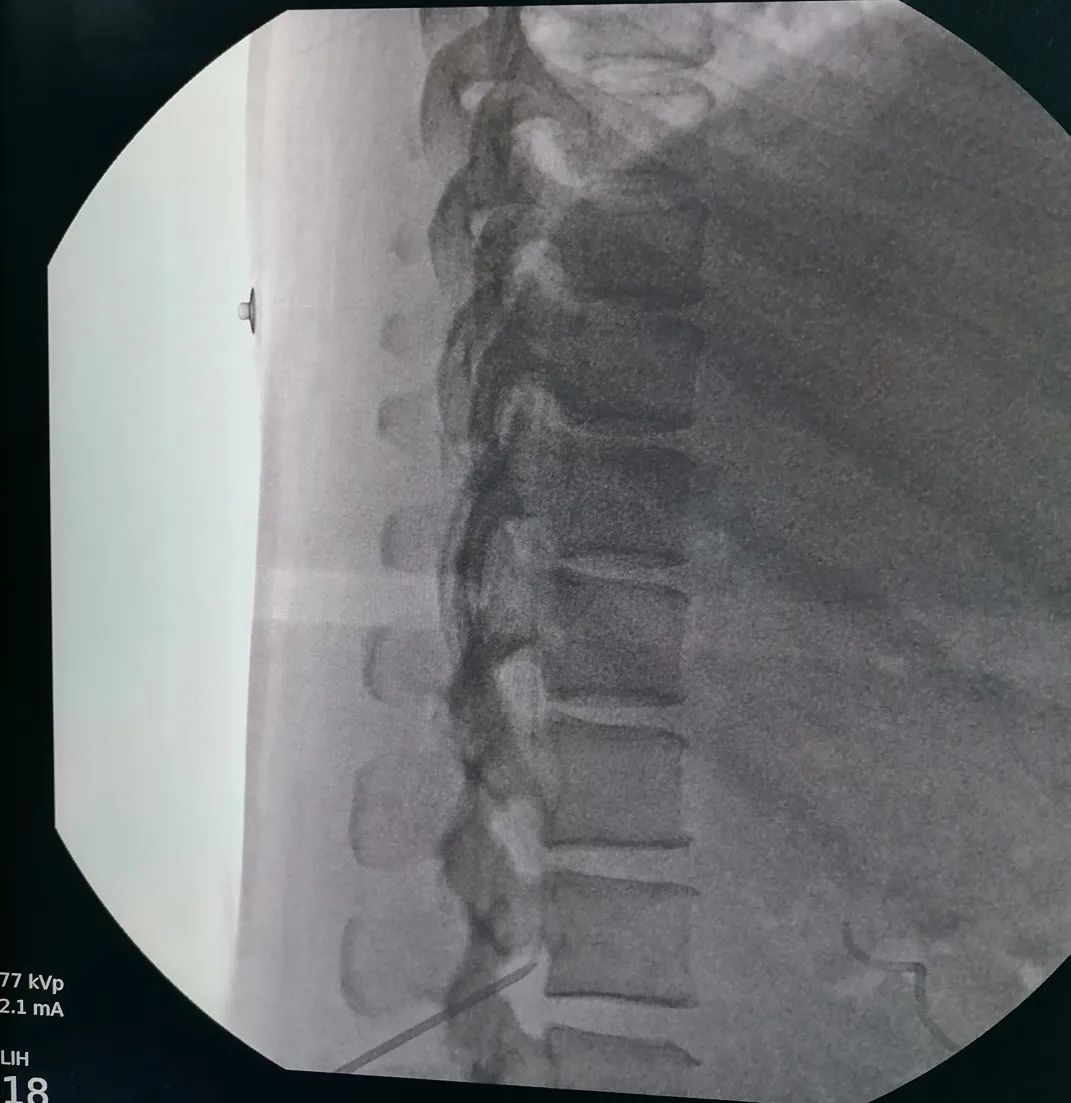

3、手术在C型臂引导下进行,微创操作,手术创伤小。